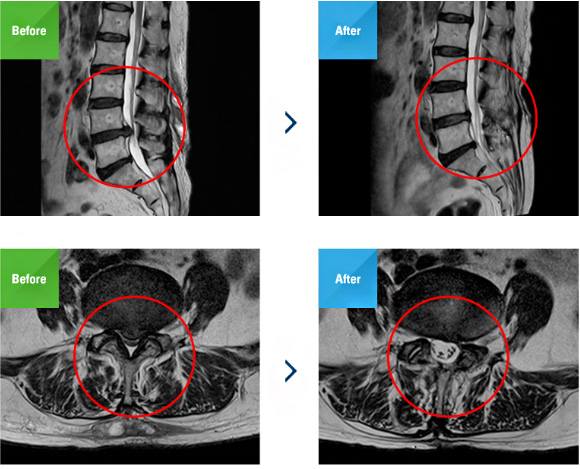

최소침습 미세현미경 디스크 제거술은 기존의 디스크 수술방법인 미세현미경 디스크 제거술을 보완한 수술법으로 최소침습으로 시행하여 절개부위가 작고 수술시간이 단축되며 출혈도 훨씬 적습니다. 아주 미세한 절개(1.5cm) 후 튜브를 삽입하여 수술부위에 정확히 위치시킨 뒤 미세현미경을 통해 내부를 보면서 신경을 압박하는 디스크를 제거합니다.

기존 현미경 하 감압수술은 피부와 근육을 모두 절개하고

디스크를 제거해야 했지만, 최소 침습 미세현미경 수핵

제거술은 피부만 절개한 후 1.5cm 두께의 특수관을 통해

미세현미경으로 신경을 압박하는 디스크를 제거합니다.